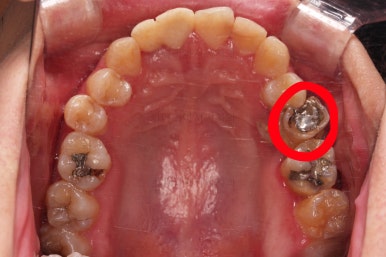

초진 시 입안의 모습입니다.

화살표는 결손 부위, 동그라기믄 유치잔존과 매복치아 부위입니다.

동그라미는 유치가 있는 상황이었는데요. 잇몸도 많이 파괴되어 있었고, 유치 자체의 상태도 좋지 못했어요.

동그라미 부분은 상한 유치가 보이는데, 그 하방으로 영구치가 매복되어 올라오지 못하고 있는 상태였어요.